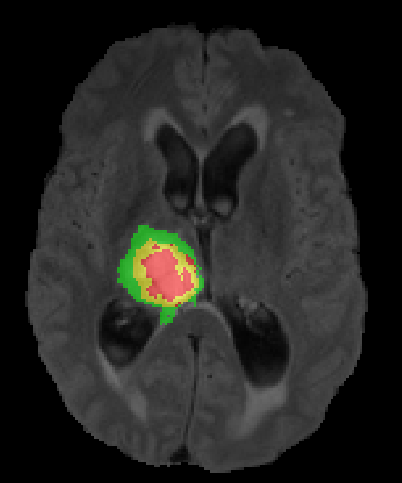

We argue that the sub-optimal paradigm of processing different abstractions within a single CNN pipeline can be remedied through the effective processing of information in a structured manner. Consequently, we devise strategies for disentangling the edge and texture information within a single training pipeline. Figure 2 illustrates how our proposed module, dubbed EG-CNN, can be paired with any existing CNN encoder-decoder to improve segmentation quality near intensity edges. We have applied our EG-CNN to the tasks of brain and liver tumor segmentation in medical images (Figure 3).

Edge-Aware 2D Image Segmentation Networks

[49; 48]: Fully convolutional neural networks (CNNs) have proven to be effective at representing and classifying textural information, thus transforming image intensity into output class masks that achieve semantic image segmentation. In medical image analysis, however, expert manual segmentation often relies on the boundaries of anatomical structures of interest. We propose 2D edge-aware CNNs for medical image segmentation. Our networks are designed to account for organ boundary information, both by providing a special network edge branch and edge-aware loss terms, and they are trainable end-to-end. We validate their effectiveness on the task of brain tumor segmentation using the BraTS 2018 dataset. Our experiments reveal that our approach yields more accurate segmentation results, which makes it promising for more extensive application to medical image segmentation. -

3.

Plug-and-Play Edge-gated 3D Image Segmentation Networks

[50]: We propose a plug-and-play module, dubbed Edge-Gated CNNs (EG-CNNs), that can be used with existing encoder-decoder architectures to process both edge and texture information. The EG-CNN learns to emphasize the edges in the encoder, to predict crisp boundaries by an auxiliary edge supervision, and to fuse its output with the original CNN output. We evaluate the effectiveness of the EG-CNN against various mainstream CNNs on the publicly available BraTS19 dataset for brain tumor semantic segmentation, and demonstrate how the addition of EG-CNN consistently improves segmentation accuracy and generalization performance. -